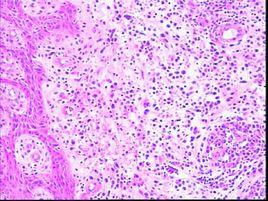

ALCL患者常見症狀為:發熱、盜汗、疼痛。體徵為消瘦、淺表淋巴結腫大、壓痛,結外者病變局部出現腫塊。病變起始部位以頸部、腋下及腹股溝淋巴結腫大多見,結外以皮膚、肺、胃腸道、骨等常見,偶也可原發於肝、脾及軟組織等。約5%的病例累及骨髓。就診時多數病人達臨床II、III期。